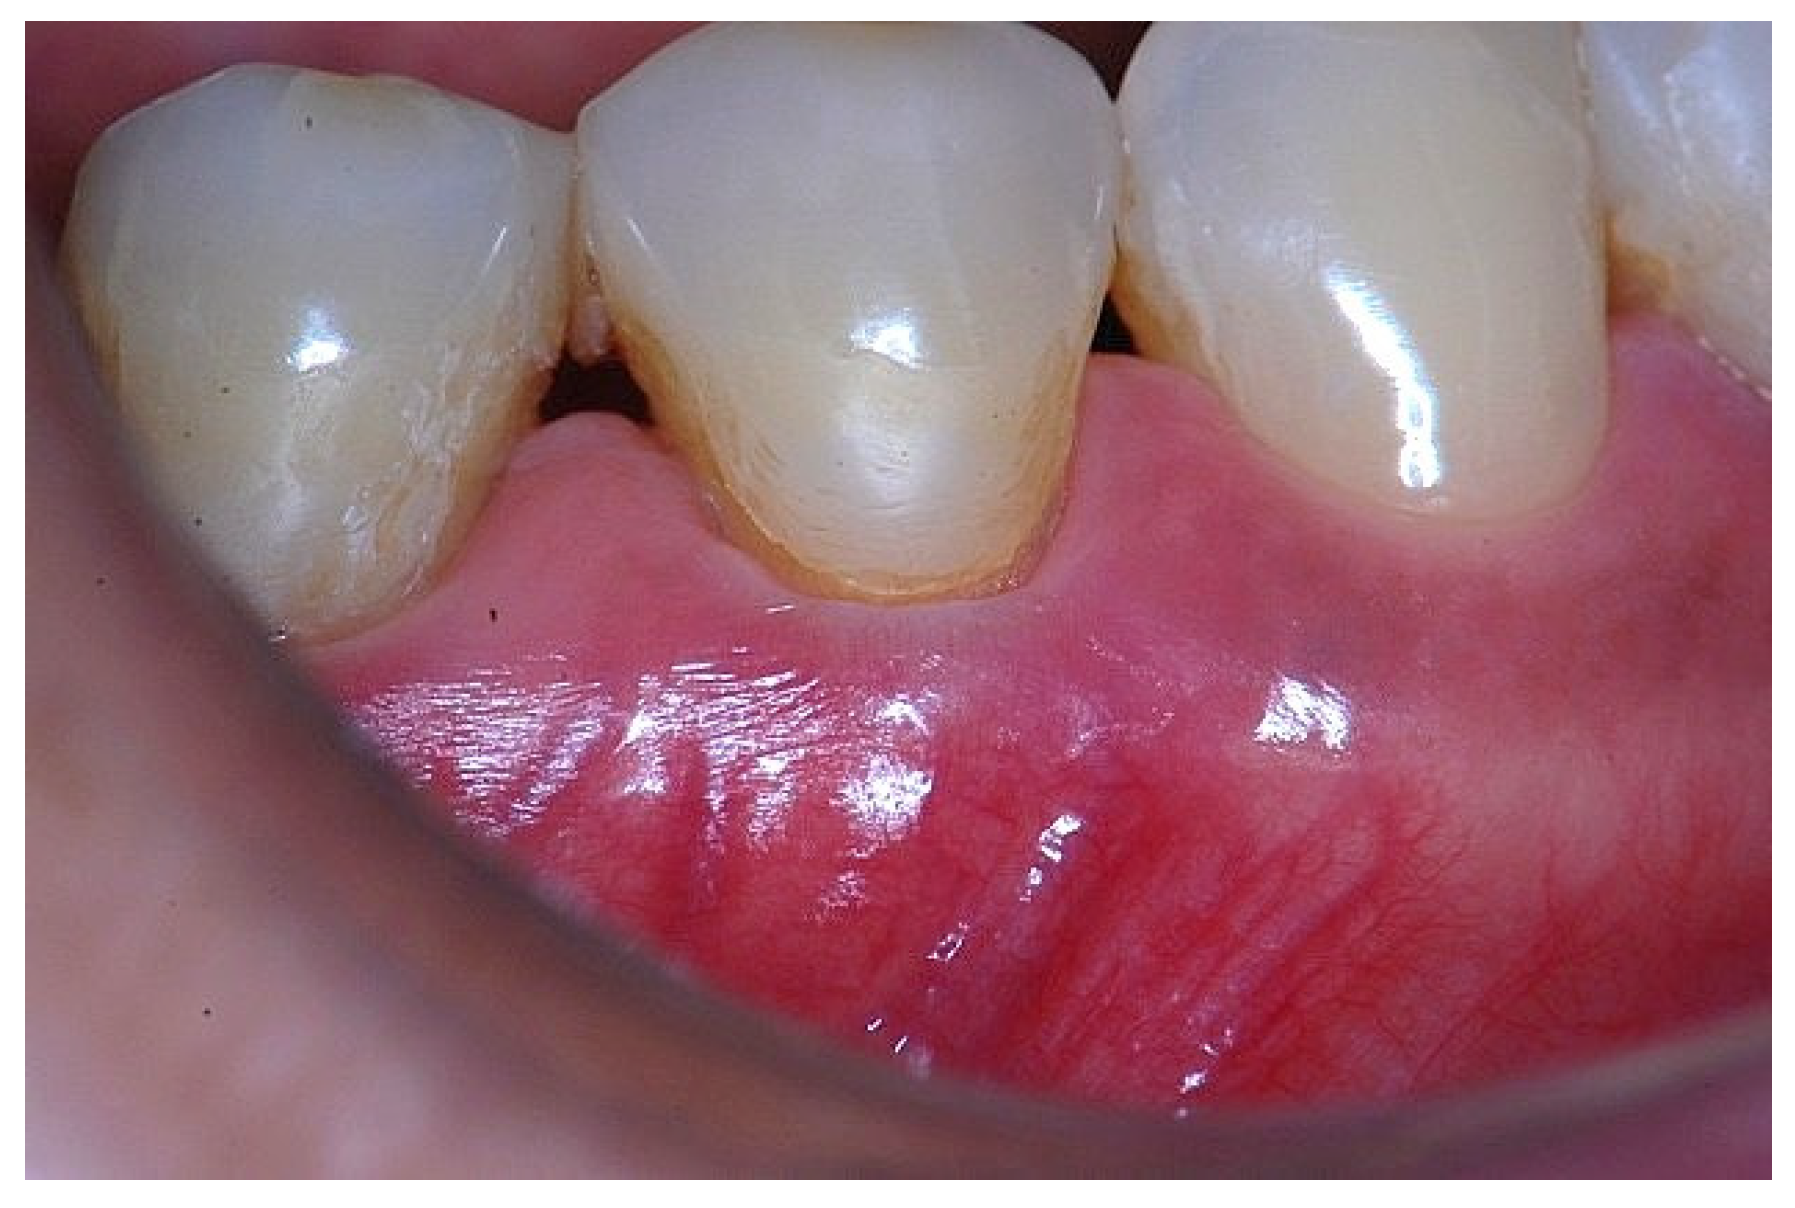

Figure 2. Clinical view of tooth #29 showing an insufficient width of attached gingiva on the facial aspect.

In a clinical scenario characterized by 2 mm of keratinized tissue and a sulcus depth of 1 mm, a stable and mechanically resistant connective tissue attachment is not present [1]. This is attributable to the fact that most connective tissue fibers inserting into the root surface are associated with non-keratinized, mobile mucosal tissues (Figure 1), which are elastic in nature and therefore incapable of stabilizing the gingival margin (Figure 2 and Figure 3). In contrast, when these fibers are embedded within keratinized tissue, they are firmly anchored to both the tooth and alveolar bone and are comparatively immobile, thereby contributing to gingival margin stability (Figure 4, Figure 5 and Figure 6).